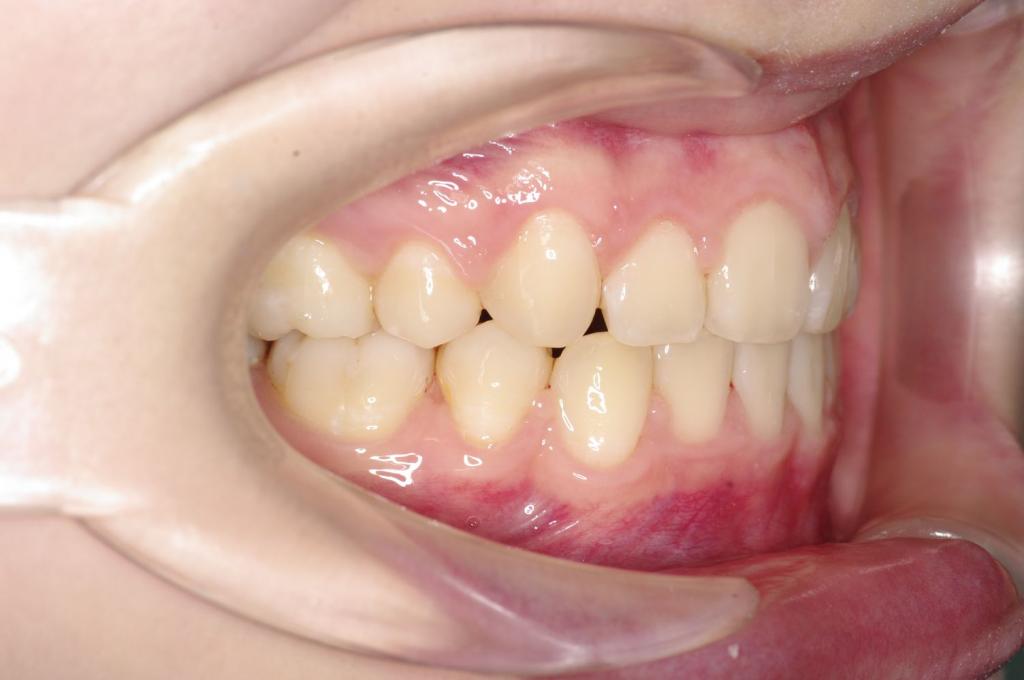

前歯、出っ歯・開咬の矯正治療

(治療期間、治療前後写真、治療方法、費用)WORKS